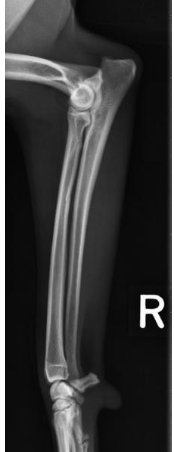

what position do we put the animal in for a lateral view of the radius and ulna?

lateral recumbency with the affected limb down (slightly flex the elbow and pull limb cranially)

what radiographic view of the radius and ulna is shown?

lateral view